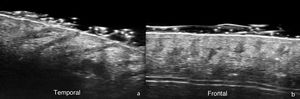

In the field of trichology—normal hair follicles are described ultrasonographically as oblique hypoechoic bands in the dermis that, in the anagen phase—are located in the deep dermis or even in the upper hypodermis, while in the telogen phase they are restricted to the upper dermis (Fig. 1). In the scalp, hair shafts are reported as predominantly trilaminar hyperechoic structures with an outer cuticle-cortex complex and an inner medulla.2,6 When comparing HFUS with trichoscopy, it has been reported that the number of follicular units does not differ significantly, and only their width is greater with ultrasound measurements.7 In UHFUS, the hair tracts are observed inside the follicles before emerging to the surface.2,5